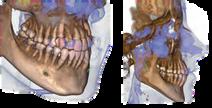

FOVs with a 10 cm diameter are essential for the study of impacted third molars because, in an adult of medium build, the distance between the third molars on the left and right, including the respective roots, the alveolar process and the surrounding bone, is at least 9 cm Reduced fields of view are useful when analysing impacted or supernumerary teeth in order to restrain the dose to the region of interest For a correct treatment planning it is indeed crucial to determine the actual position (vestibular or palatal) This is only possible with a 3D analysis, even at a very low dose, with the QuickSCAN protocol The complete 13 x 16 cm field of view allows for an accurate assessment of the upper airways, which is often useful to complete the investigation for an orthodontic treatment that does not neglect ENT problems.

Position the equipment directly on the 3D model, combine it with the STL data from intraoral scanners and define the final prosthetic project With the advanced implant planning tools* you will be able to operate safely thanks to accurate information on the amount of bone and the distance from the surrounding anatomical structures, such as the mandibular canal, defining a minimum safety distance